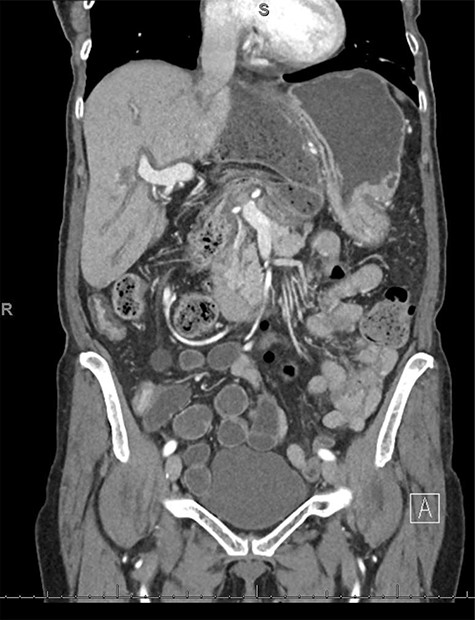

An 80-year-old female with past medical history of Crohn’s disease (diagnosed in 1998 and managed with Adalimumab) and no prior abdominal surgical history who presented with 1-day history of severe epigastric pain associated with nausea and emesis. Her last colonoscopy was 3 years ago (unremarkable), and last Crohn’s flare was a 1 year beforehand. On examination, patient’s abdomen was soft with severe epigastric tenderness and an appreciable bulge. Labs showed normal lactate (1.1) but mild leukocytosis of 12.5 and no other gross lab abnormalities. Patient underwent computed tomography (CT) scan of abdomen and pelvis which showed a transverse colon herniating through the FOW and causing a closed-loop obstruction (Figs. 1–3). Patient was immediately decompressed with a nasogastric tube and was emergently taken to the operating room for a diagnostic laparoscopy. Intraoperatively, the transverse colon was noted to have herniated through the FOW into the lesser sac. The incarcerated transverse colon appeared immensely dilated and hyperemic. With careful traction and gentle counter pressure, the transverse colon was completely reduced from the FOW back into the abdominal cavity. On inspection after reduction, the small and large bowel appeared grossly viable and well-vascularized along with adequate peristalsis. The FOW was closed with 2-0 ethibond running suture by suturing the peritoneum adjacent to the portal triad down to the retroperitoneum just lateral to the inferior vena cava. The patient tolerated the procedure very well and brought to the recovery room in stable condition. Postoperatively, the patient did very well. On postoperative Day 1, the patient was discharged home. Subsequently, the patient was seen in the office on postoperative follow-up Day 7 and was found to be doing well with no complaints.

CT coronal view showing proximal and distal loops of transverse colon are seen in the region of the foramen of Winslow.